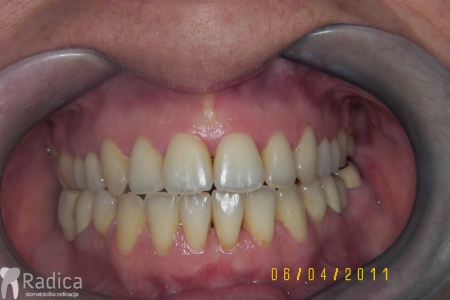

U galeriji slika su prikazani klinički slučajevi ovakvih odraslih pacijenta bilo da se radi samo o ortodontskoj terapiji ili predprotetskoj ortodonciji.